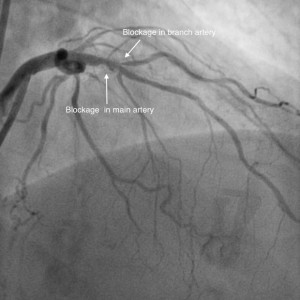

Bifurcation stenting is done in patients where the narrowing (blockage) occurs at the level of division of two arteries. The idea of stenting is not to compromise the flow in the branch artery. There are various types of techniques to be used depending on the location of the narrowing to decide between if one or two stents are needed. There are also presently dedicated bifurcation stents, which are being used to help the situation. Strategic planning with the help of angiogram is the key to do this procedure to achieve good blood flow in both branches of the arteries. Most of the bifurcation stenting can be done via the wrist.